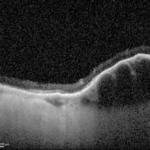

Figura 6. Ecografia Bscan all’occhio sinistro.